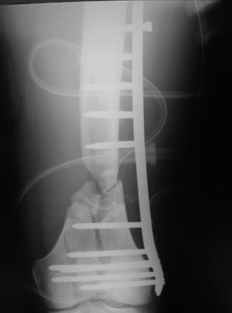

This is what we have done... As generally true for LISS look at the bone not the hardware.

There are two more srews above. The one not completely in got damaged head.

I would not say that the LISS is superior to the nail. If I would, I had not post original mail. I wanted to generate discussion. Your option is a very viable one. I feel a little bit shaky the distal femur, but it is just gut feeling no science behind it. Any way nice fixation, congarts!